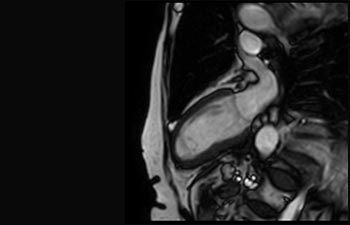

Enhanced diagnostic confidence in neuro oncology

Find the right clinical applications for your needs